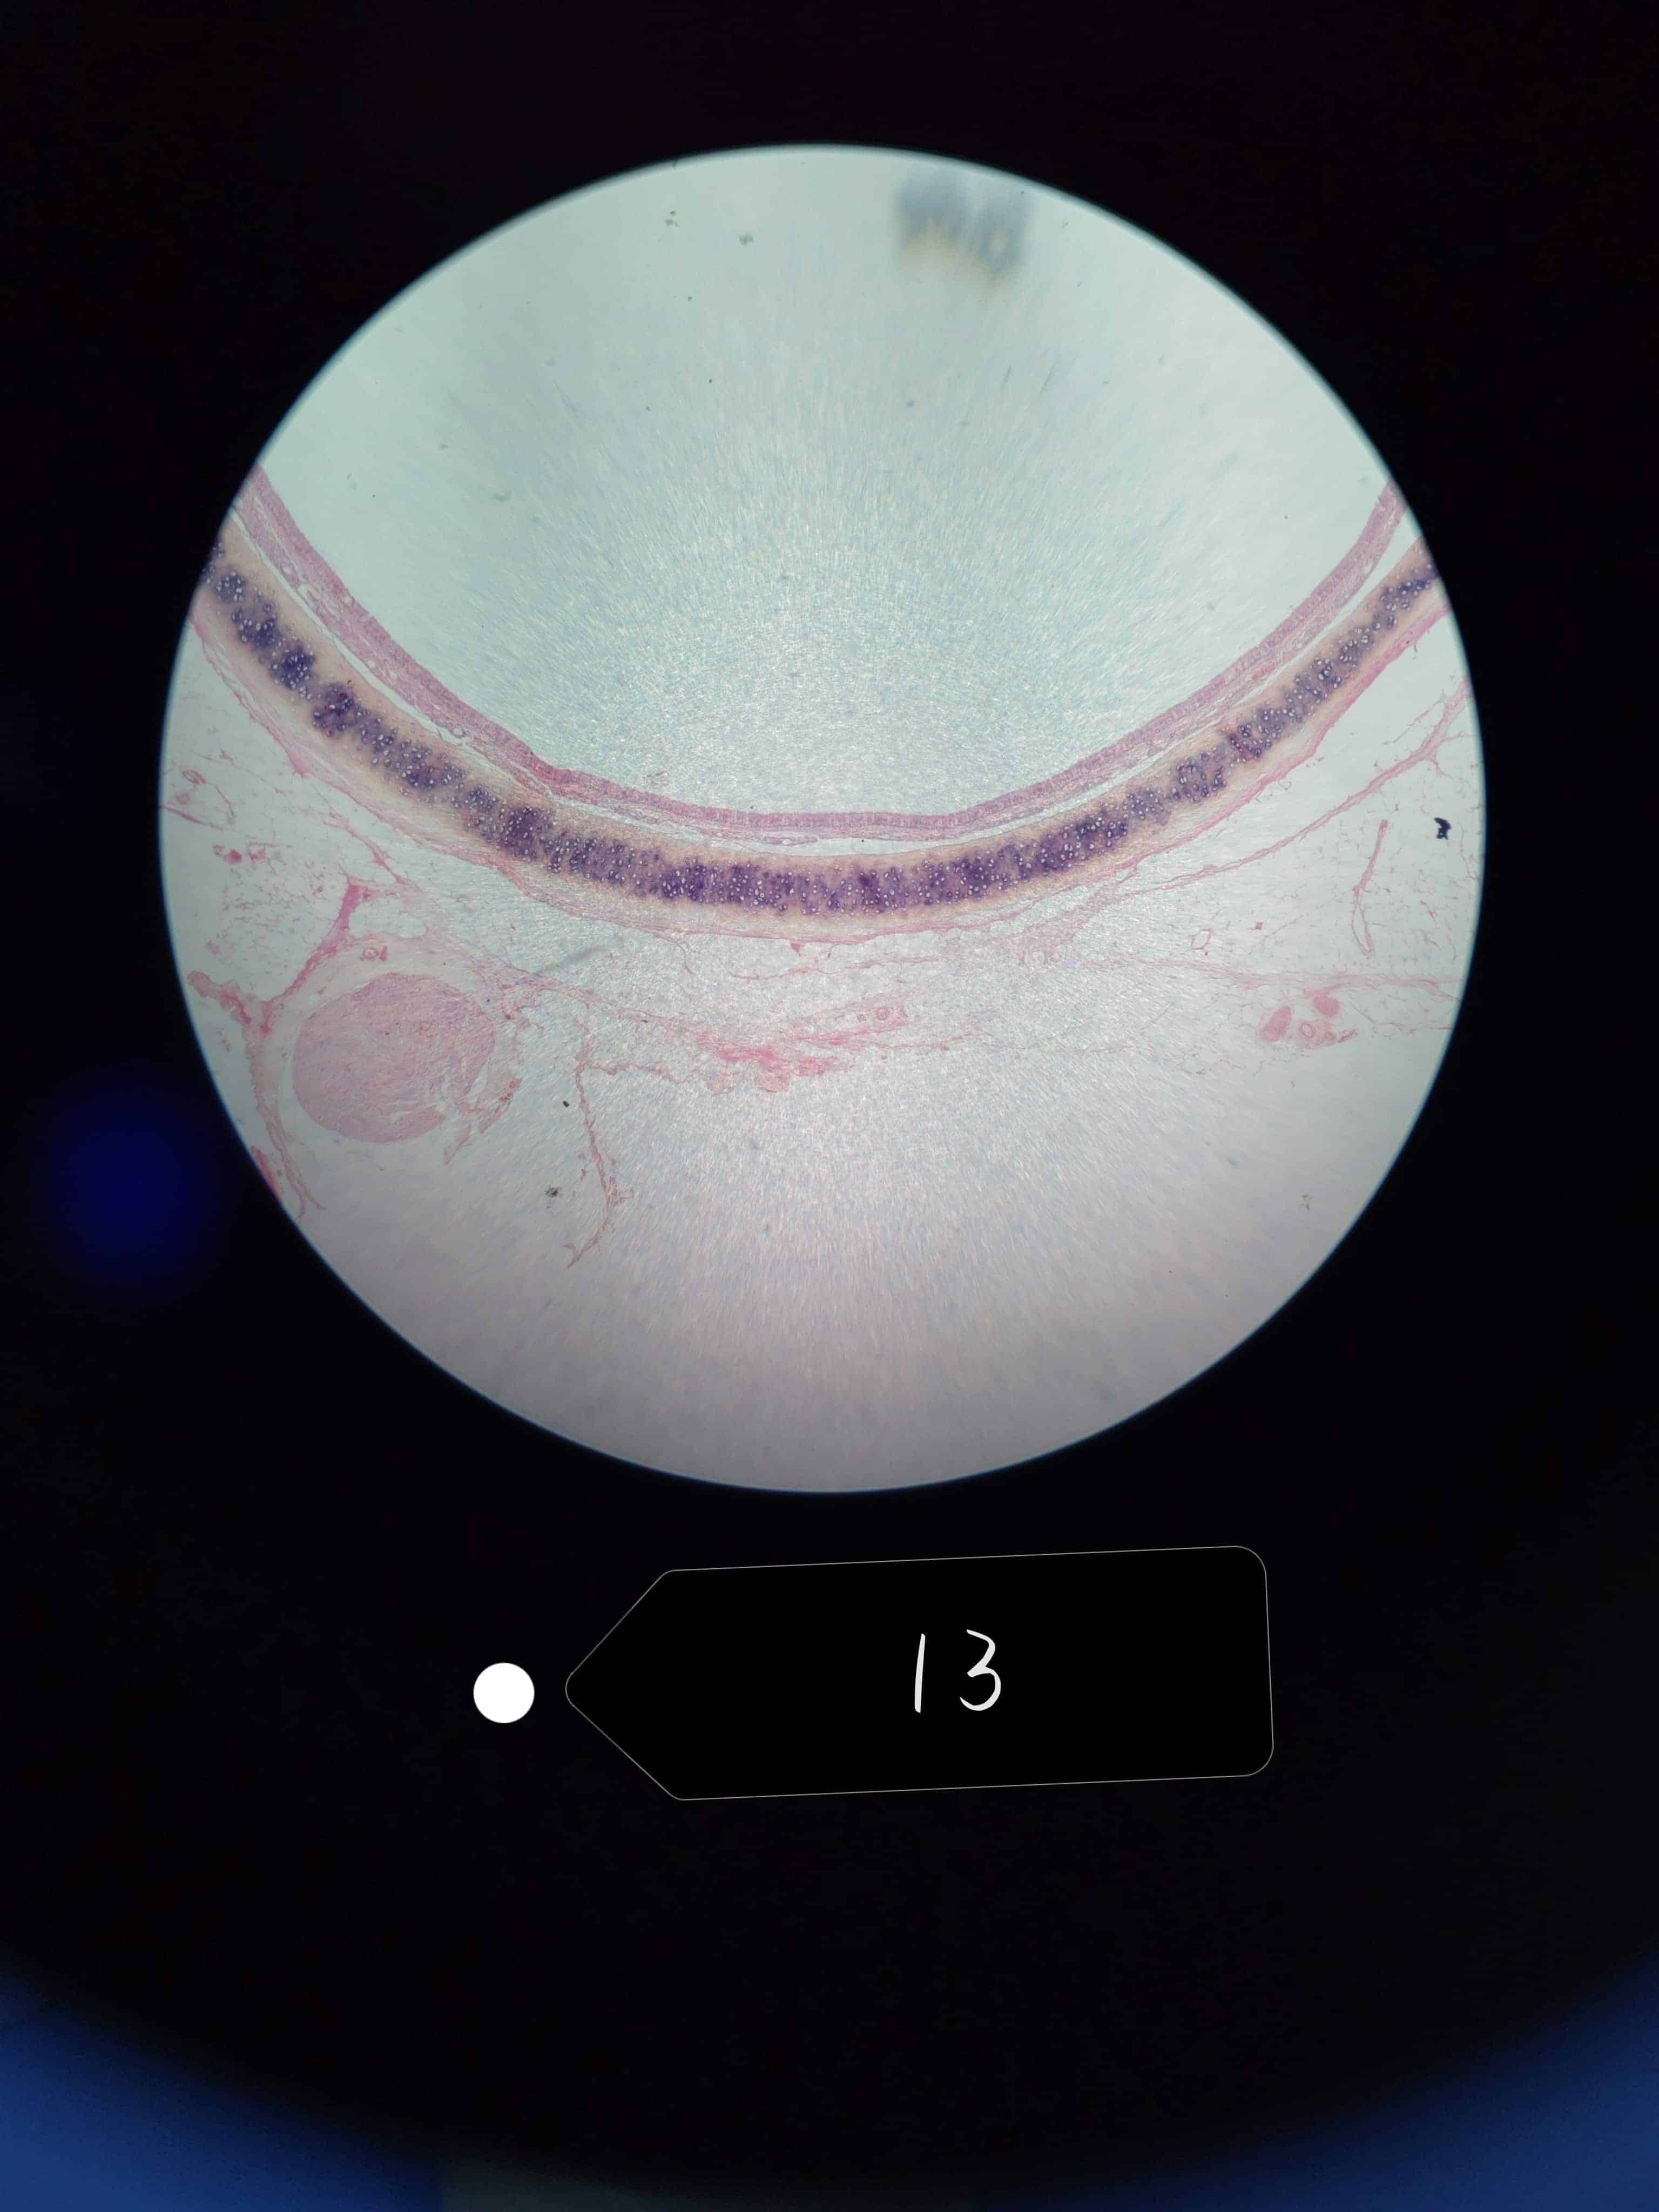

卵巢

周围部分较厚可见大小不等的卵泡

初级卵母细胞和卵泡细胞之间有透明带